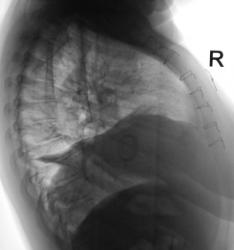

Неделю тому, пациентка выписана из терапевтического отделения, где находилась на стационарном лечении, по поводу пневмонии. Сегодня пациентка направлена на рентгенологическое исследование ОГК с диагнозом "Пневмония". Произведена рентгенография в стандартных проекциях - прямая и правая боковая, которая дополнена томографией в боковой проекции.

А я именно с операцией и связываю: либо это организовавшийся базальный гидроторакс справа, либо релаксация правого купола диафрагмы вследствие повреждения диафрагмального нерва. Конечно нужна КТ, но кое-что можно сделать и до этого.

2. Взять пациента за экран, оценить подвижность правого купола диафрагмы. Свободная жидкость есть вряд ли: на боковых томограммах она бы растеклась, а этого нет.

Если допустить, что правая 1/2 диафрагмы поднята – с этим, кажется, все согласны – а причиной ателектаза является плевральный выпот над ней, (как полагает Dr.Mario), то непонятно почему выпот, сдавливая нормальную упругую лёгочную ткань сегментов н/д и с/д, позволяет диафрагме подняться, ведь на неё он давит ещё больше. Но вот если причина ателектаза обтурация бронхов, а выпота немного, и занимает он только часть освободившегося в грудной полости объёма, поднятие диафрагмы закономерно.

Оказывается во время операции был пересечен нерв. Вот рентгенограммы - 1 сделана после операции, вторая - через 1 месяц.

Ну уж коли за 10 мес. динамики нет, значит всё дело в релаксации диафрагмы, а выпота мало и обтурции бронхов, видимо, нет. Поджаты и уже не расправятся S4, S5, S7, S8, S9, S10.